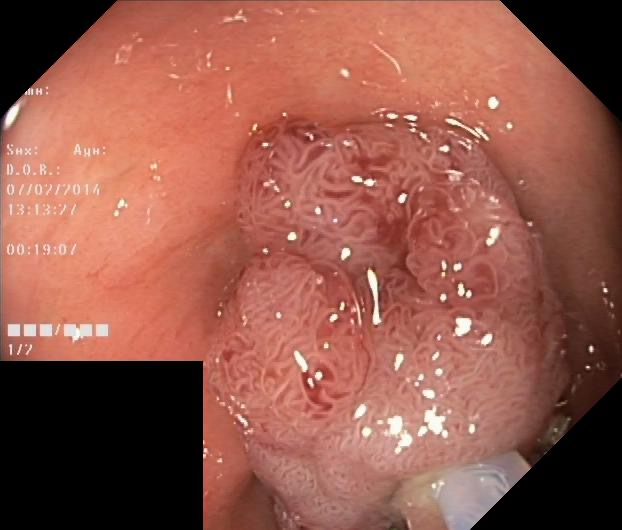

While large models have achieved significant progress in computer vision, challenges such as optimization complexity, the intricacy of transformer architectures, computational constraints, and practical application demands highlight the importance of simpler model designs in medical image segmentation. This need is particularly pronounced in mobile medical devices, which require lightweight, deployable models with real-time performance. However, existing lightweight models often suffer from poor robustness across datasets, limiting their widespread adoption. To address these challenges, this paper introduces LV-UNet, a lightweight and vanilla model that leverages pre-trained MobileNetv3-Large backbones and incorporates fusible modules. LV-UNet employs an enhanced deep training strategy and switches to a deployment mode during inference by re-parametrization, significantly reducing parameter count and computational overhead. Experimental results on ISIC 2016, BUSI, CVC-ClinicDB, CVC-ColonDB, and Kvair-SEG datasets demonstrate a better trade-off between performance and the computational load. The code will be released at https://github.com/juntaoJianggavin/LV-UNet.